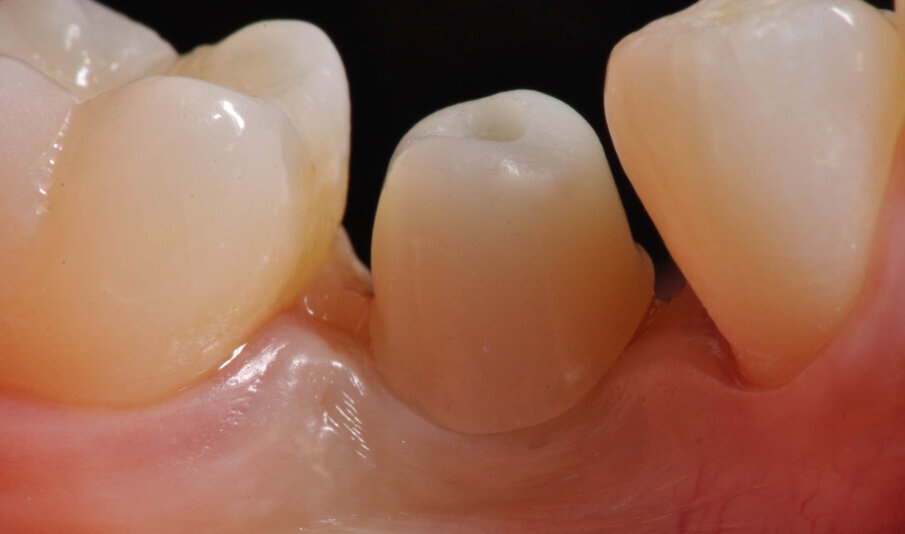

Fig. 13_Lo strato inferiore abutment serrato in posizione realizzato in Enamic IS.

Fig. 15_Lo strato superiore realizzato in Vita Trilux Forte (sx).

Fig. 16_Lo strato superiore realizzato in Vita Trilux Forte (dx).